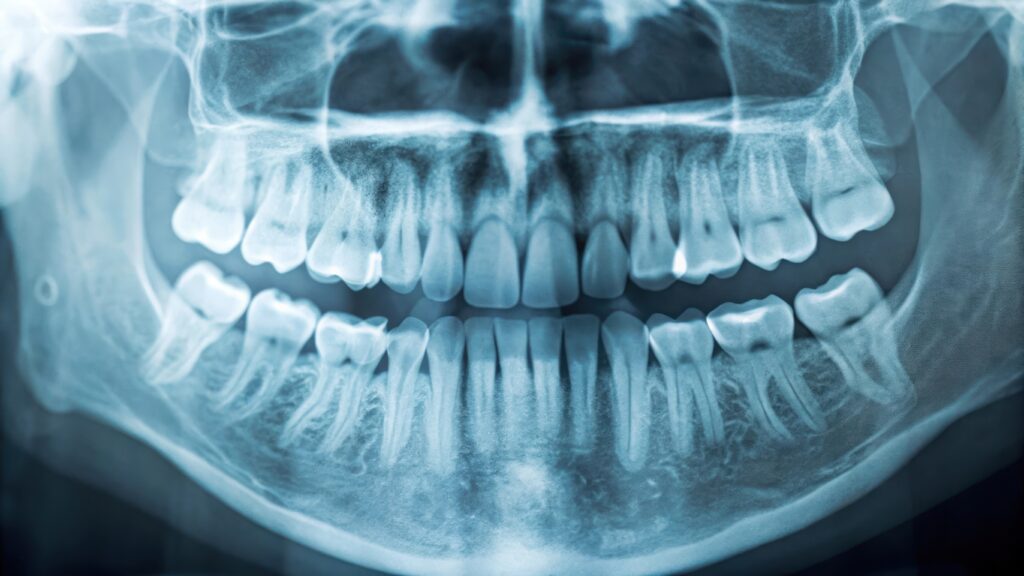

親知らずの位置、上顎洞・顎骨の広範囲の確認:パノラマが有用です。ただしパノラマは“全体像”が得意で、初期むし歯の検出は不得手です。必要に応じてデンタルやバイトウイングを併用します。

パノラマ:広範囲に全体像を把握。親知らず、顎骨、上顎洞などの評価に有用。ただし初期むし歯の検出は不得手。